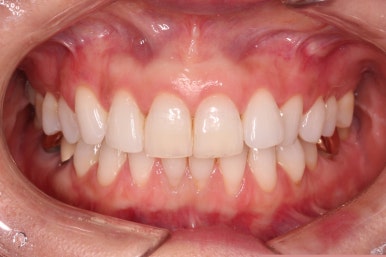

초진 시 얼굴 모습입니다.

전반적으로 모두 양호합니다. 입이 편안하게 다물어지는 느낌, 옆라인, 심지어는 중앙선까지 양호합니다.

단 하나, 작은 앞니 하나가 톡 튀어나와 있는 부분이 미적으로 좋지 못한데요.

환자분이 원하시는 만큼 가지런해졌고, 부가적으로 생길 수 있는 부분들도 수용 가능한 선에서 잘 마무리가 되었습니다.

3개월이라는 빠른 기간 내에(심미보철 보다 약간만 더 긴 시간) 치아의 손상없이 마무리를 잘 했습니다.

아래 앞니는 부분교정까지는 원하지 않으셔서 약간 다듬어 드리고 종료했습니다.